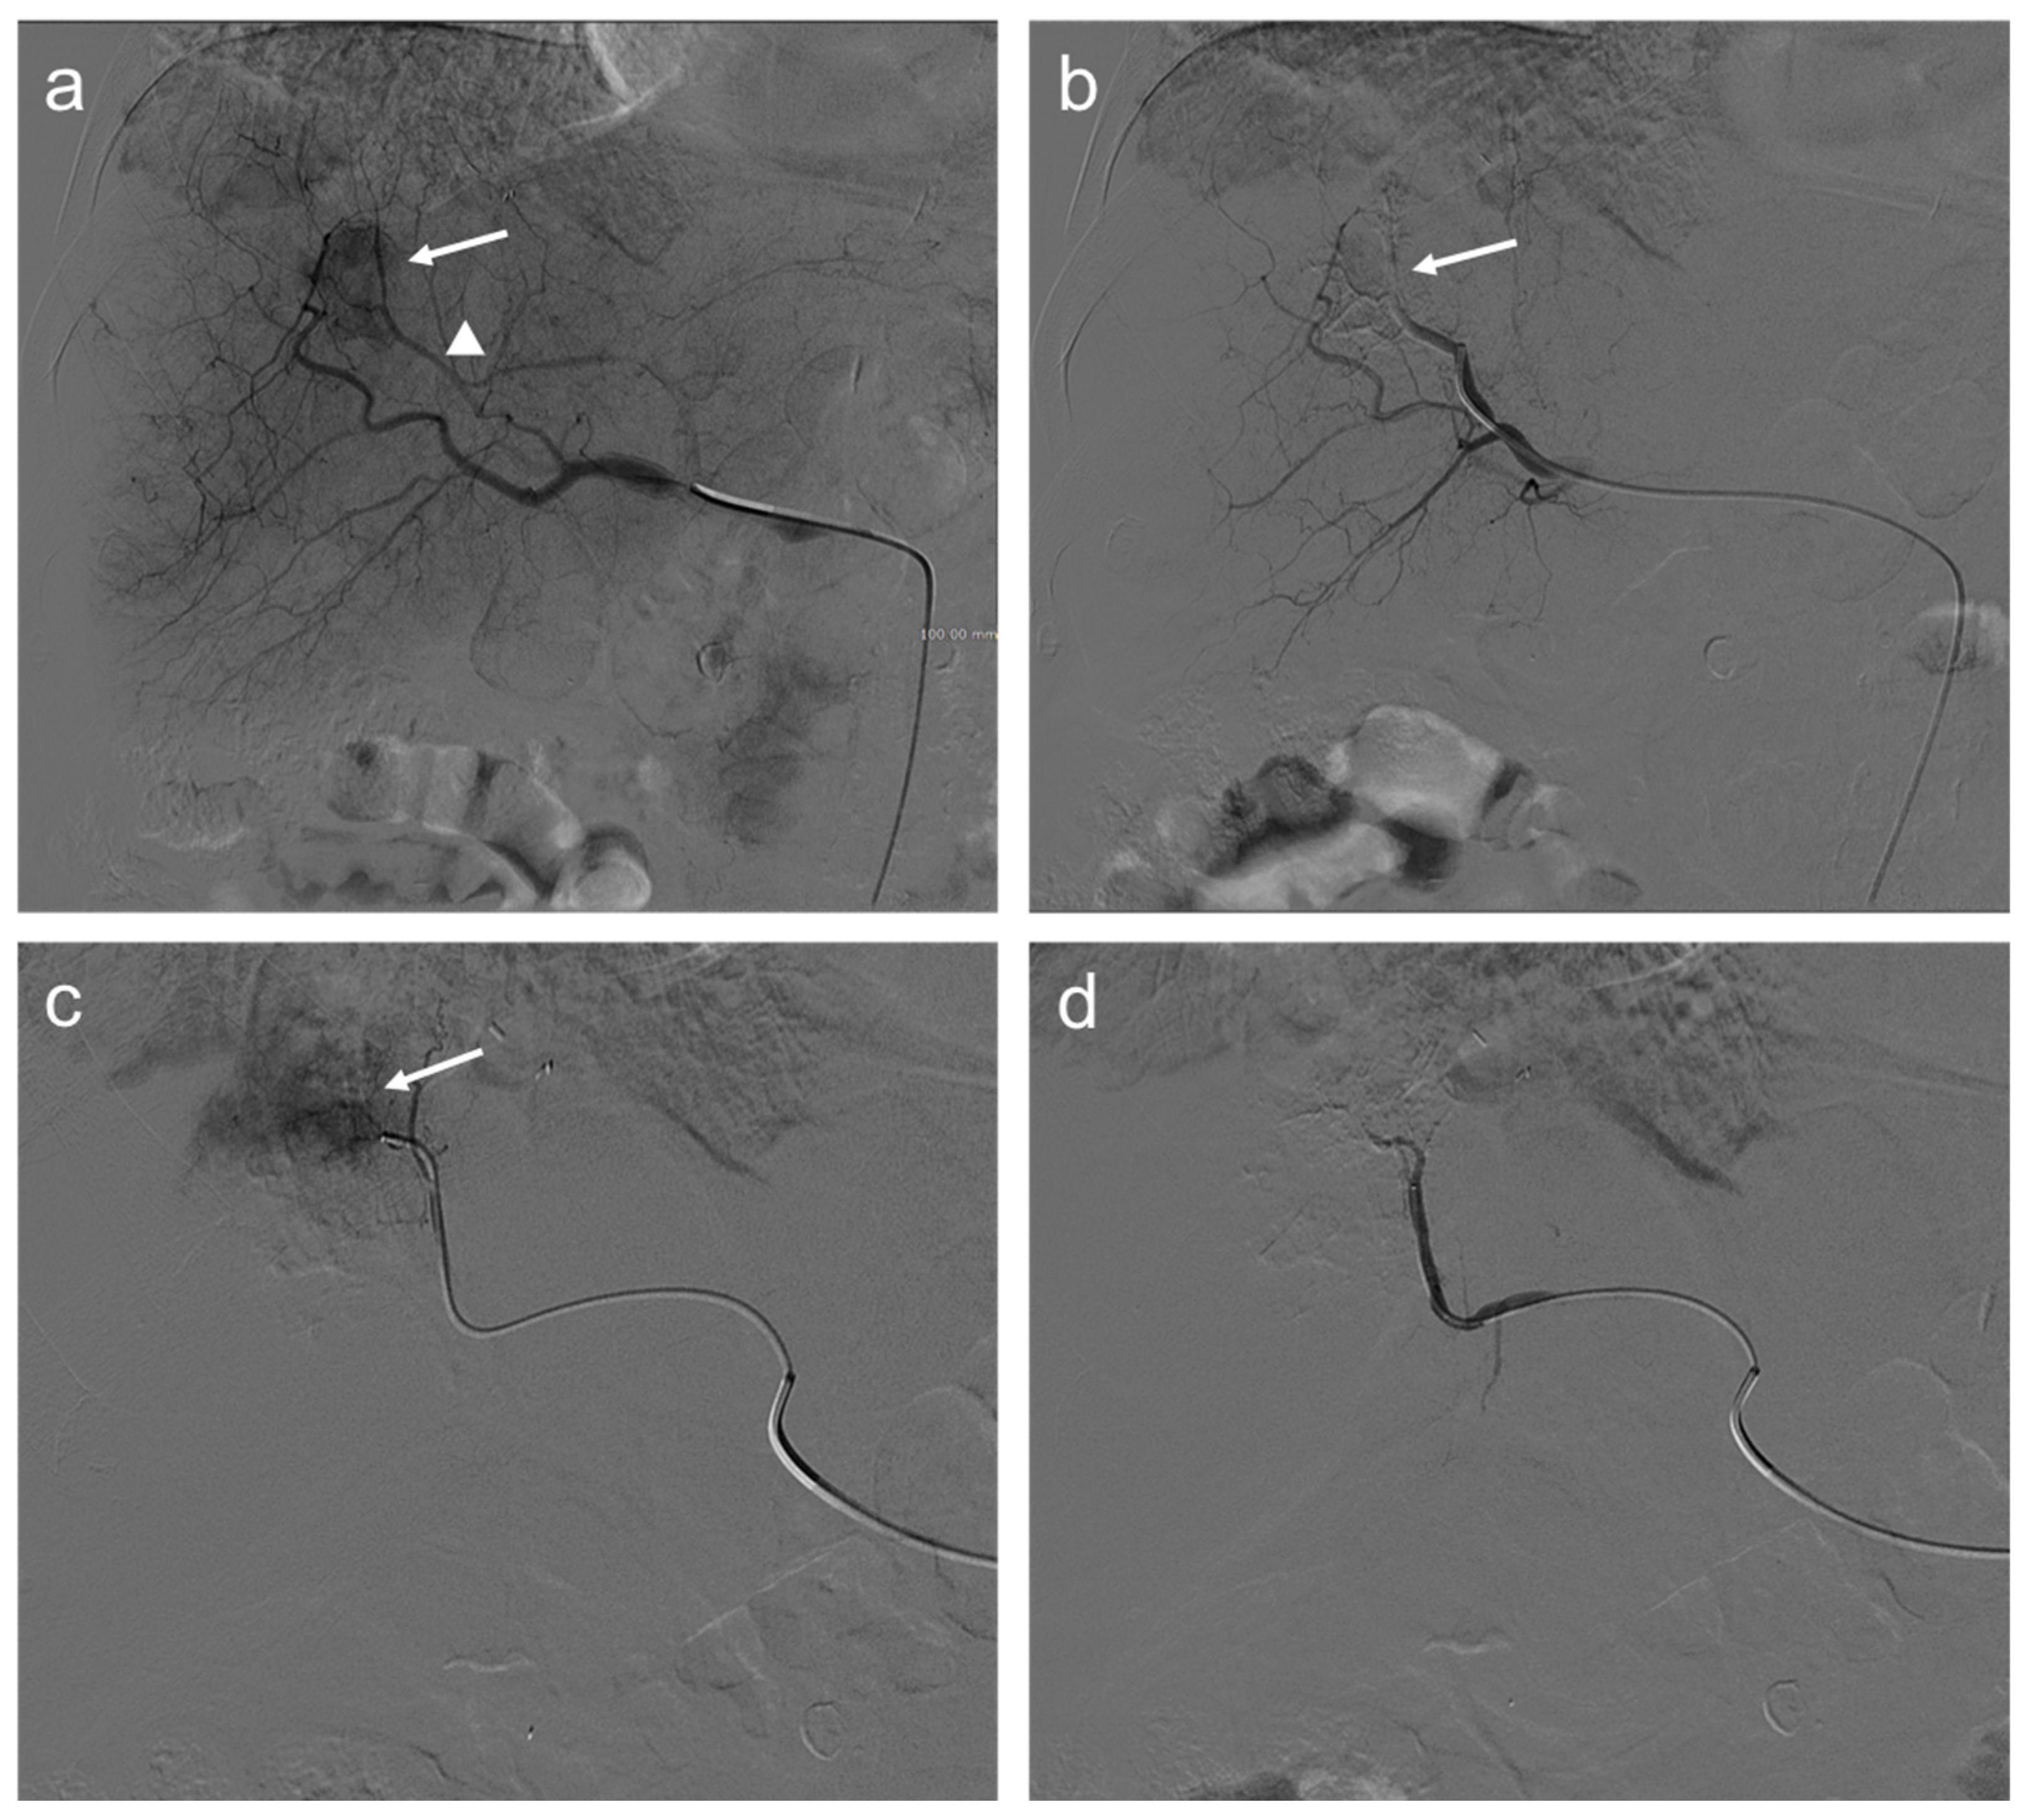

2. TACE Technique